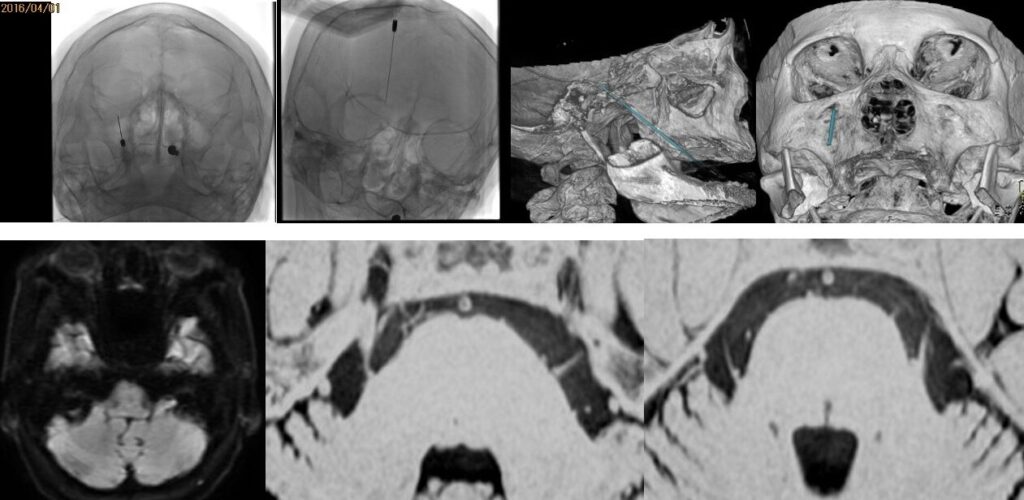

87歳女性、繰り返しブロックを行いガンマナイフも行った、難治生三叉神経痛を手術しました。高齢ですが無事一発治癒しました。 2025 12/11 顔面痙攣・三叉神経痛 2025年12月11日87歳でできるだけ手術を避ける方針で、投薬、ブロック、ガンマナイフを行ってきましたが、とうとう手術になりました。幸い合併症や脳梗塞が生じることなく治癒しました。最初から手術すべきと言う人もいますが、私は、やはり本人の納得が一番大切だと思います。ScreenshotScreenshot 顔面痙攣・三叉神経痛 よかったらシェアしてね! URLをコピーしました! URLをコピーしました! 251013月 休日なので小浜、大飯町、美浜へ温泉&ドライブ 251016木 高嶋浩央先生が入局を決心してくれました この記事を書いた人 kikuta 関連記事 2603月 67歳男性の右顔面痙攣を手術しました。 2026年3月22日 2603月 58歳女性の左顔面痙攣を治療しました。VAとAICAの複合型圧迫でしたがうまく治癒できました。 2026年3月21日 46歳男性、開眼できないほどのVA型左顔面痙攣を手術しました。術後まだ完全には消失していませんが痙攣は著明に軽減しました。 2026年3月3日 19歳女性の三叉神経痛を手術しました。術後痛みは消失した様子です。 2026年3月3日 左三叉神経痛の手術をしました。カルバマゼピンで抑えられい強い痛みがありましたが、手術後痛みが完全になくなり食事も取れるようになりました。 2025年12月5日 2025年8月 78歳 VA型の顔面痙攣の神経減圧術を行いました。M-TEPを併用し無事治癒しました 2025年12月4日 2025年5月 テグレトールで治らない左三叉神経痛の手術を行い直後より痛みは消失しました。 2025年9月25日 畑山式MVDハンズオンセミナーに東野先生と参加してきました 2025年3月22日